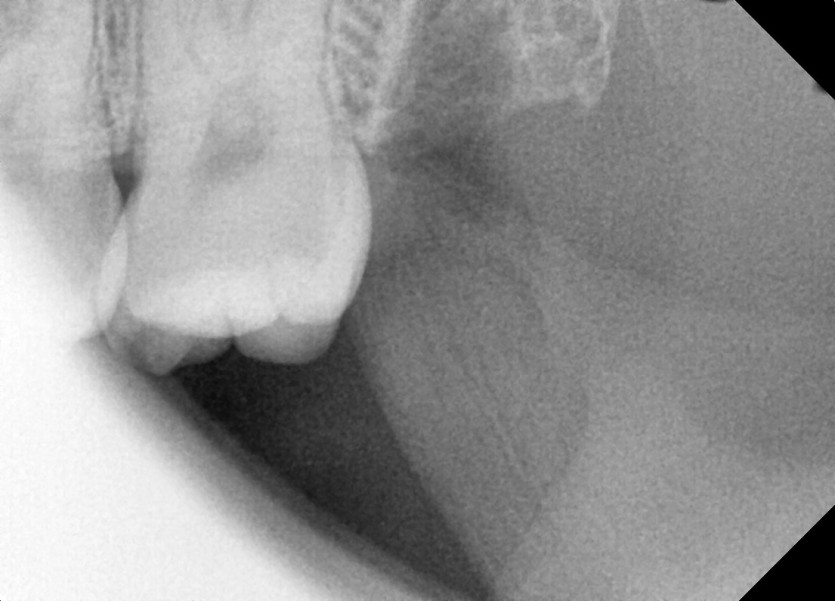

#28,38 사랑니 발치

구강외과 전문의가 당일 발치했습니다.